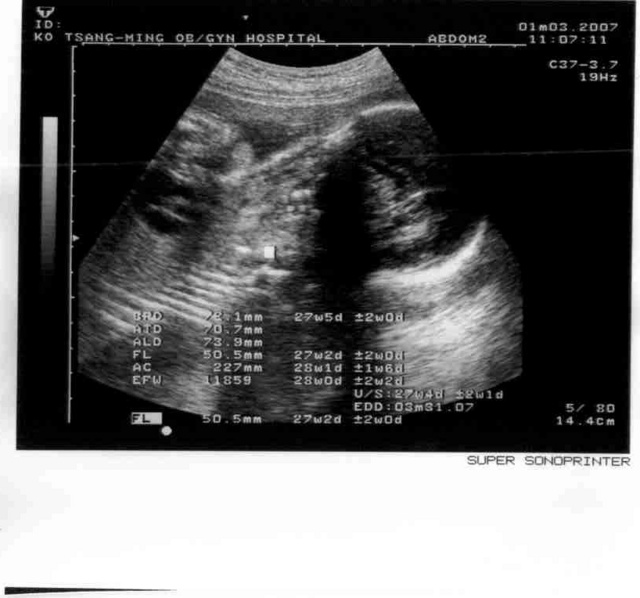

2007.01.29

從瑞士回來了,小寶寶很健康,準備要轉去台大醫院產檢和生產準備了,也是照臉,一切正常,1600g。